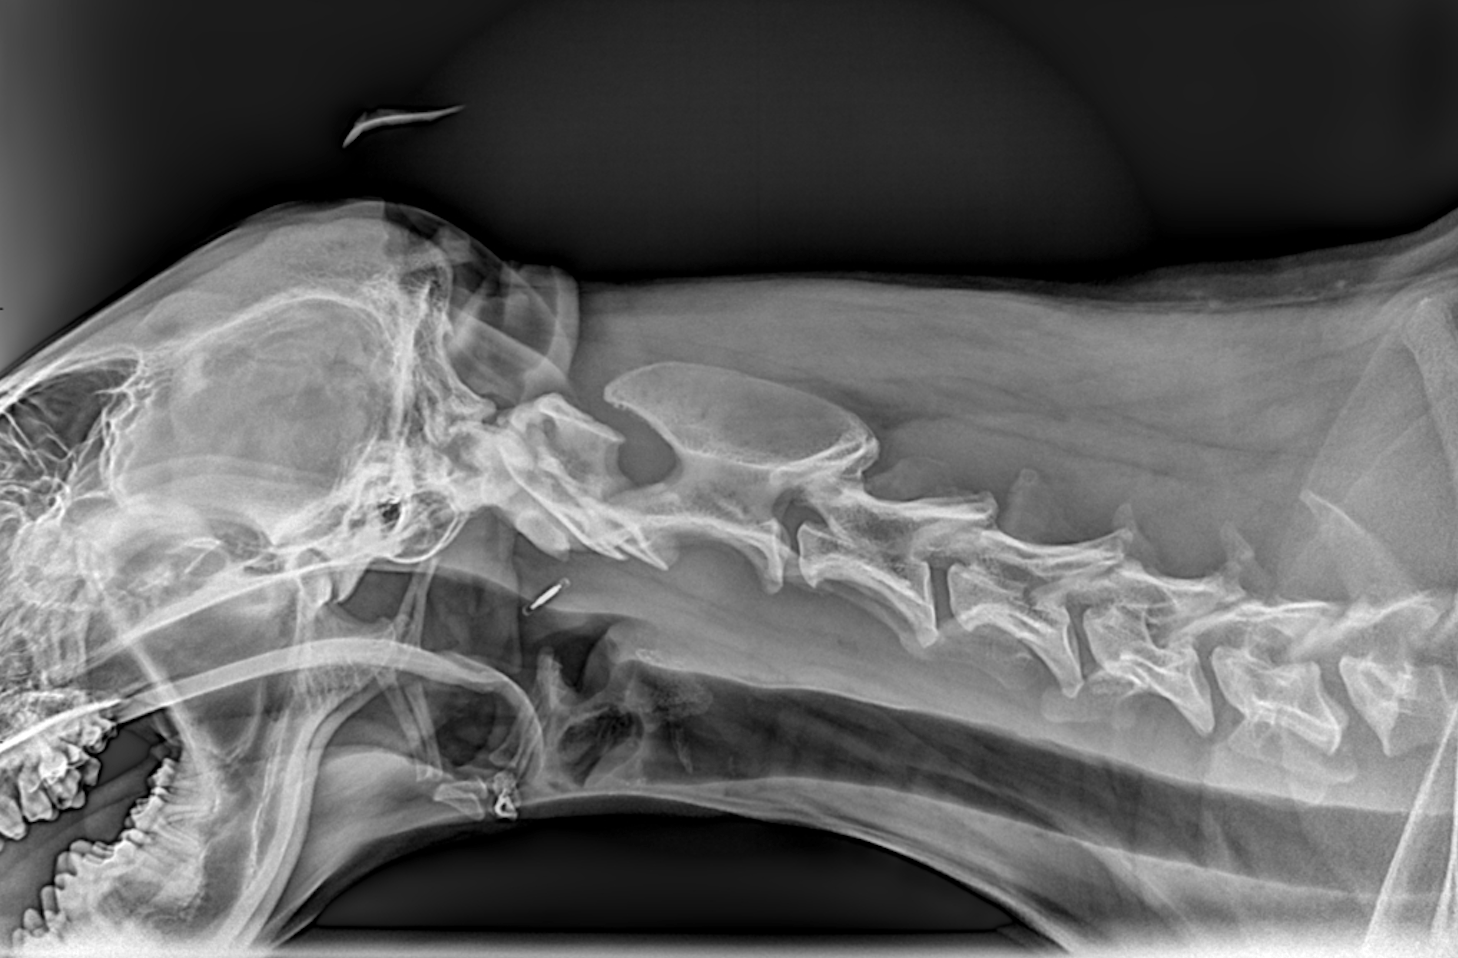

Tra i servizi che l’Ospedale Veterinario Città di Conegliano fornisce, non mancano quelli di diagnostica per immagini:

ecografia, radiologia digitale, TC.

Gli specialisti Roberto De Pellegrin e Riccardo Pelizzon, in particolare, si occupano degli esami ecografici, ecocardiografici, tomografici per l'acquisizione di immagini del corpo del paziente attraverso l'esposizione a ultrasuoni o a raggi X.

Si tratta di esami non invasivi né dolorosi, che possono essere eseguiti molto rapidamente.